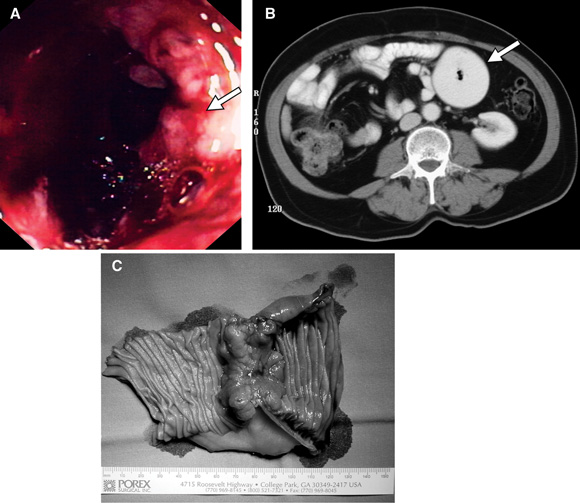

A: Small bowel carcinoma detected on push enteroscopy (Patient 1). B: Abdominal CT scan showing a large dilated small bowel loop in the left upper quadrant (Patient 2). C: Operative specimen showing a localised, constricting cancer (Patient 2).

Patient 1 A 77-year-old woman was referred to us for an urgent surgical opinion regarding an abdominal mass. Fifteen months previously, she had been referred to a major metropolitan hospital with symptomatic iron deficiency anaemia, and weight loss of 5 kg in 6 months. Gastroscopy, colonoscopy and abdominal CT scan were unremarkable. There were no clinical features to suggest malabsorption, nutritional deficiency or inflammatory bowel disease. A diagnosis of angiodysplasia was considered, although there was no direct evidence of this. The patient received a 5-unit blood transfusion and iron supplements. During the 7 months after initial presentation, she was seen in medical outpatient clinics six times. Over the next 8 months, she was admitted six times, transfused 13 units of red cells, and given two iron infusions. A labelled red cell scan showed no gastrointestinal bleeding. An abdominal ultrasound was unremarkable. Results of investigations for coeliac disease and pernicious anaemia were normal. A bone marrow biopsy was consistent with iron deficiency anaemia. On one occasion, the admitting registrar considered a small bowel follow-through, but this was not performed. Paroxysmal nocturnal haemoglobinuria was excluded. During the last of these admissions, a firm abdominal mass was palpated. A computed tomography (CT) scan revealed an 8 cm heterogeneously enhancing soft tissue mass in the proximal jejunum. Lymphoma was considered the most likely diagnosis, and the patient was referred to our department. Push enteroscopy revealed an ulcerated adenocarcinoma in the proximal jejunum (A). A 10 cm, poorly differentiated jejunal adenocarcinoma was resected. Eleven months after surgery, the patient has shown no further symptoms of anaemia, and no evidence of recurrence. |

Patient 2 A 68-year-old man was admitted to our department for laparotomy for a small bowel tumour. The patient had a past history of an open cholecystectomy. Twenty-eight months before admission, he had been referred to a gastroenterologist with symptoms of gastro-oesophageal reflux disease; he underwent gastroscopy, which showed reflux oesophagitis, and was treated with proton pump inhibitors. Eleven months later, he was referred to a gastroenterologist again with persistent symptoms. He was seen several times in the next 9 months, and was then admitted to a general surgical service of a metropolitan hospital with abdominal pain. A provisional diagnosis of small bowel obstruction was made, and the patient was discharged the following day once his pain had settled. Twice during the next 5 months, he presented to the emergency department with abdominal pain, nausea and vomiting. His symptoms settled with analgesia and fluids. Persistent retrosternal pain had not been helped by a variety of H2 antagonists, proton pump inhibitors or prokinetic agents. He was admitted to our surgical service after presenting on two successive days with severe epigastric pain. Upper gastrointestinal endoscopy showed severe reflux oesophagitis. The first and second parts of the duodenum were normal. Abdominal CT showed a circumferential mass in the proximal jejunum with dilation of proximal bowel (B). Small bowel follow-through then showed an annular, stenosing lesion in the region of the duodenojejunal flexure. At laparotomy, a localised adenocarcinoma was resected (C). The patient had adjuvant chemotherapy and 12 months after surgery was asymptomatic, taking no medication, and had no evidence of recurrence. |